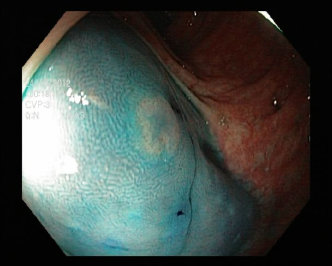

4.1.7 Gastrointestinal endoscopy

Endoscopies are used to detect diseases in the human digestive system. Images from inside the gastrointestinal tract can be used to help doctors detect diseases early. The used dataset 777https://www.kaggle.com/datasets/abdallahwagih/kvasir-dataset-for-classification-and-segmentation contains eight image categories of the digestive system obtained through the endoscopy imaging technique, as shown in Fig. 8. There are a total of 6000600060006000 images that can be used in training and testing machine learning algorithms.

Refer to caption

(a) Normal cecum

(b) Normal pylorus

(c) Normal z-line

(d) Dyed lifted polyps

(e) Dyed resection margins

(f) Esophagitis

(g) Polyps

(h) Ulcerative-colitis

Figure 8: Gastrointestinal endoscopy images.